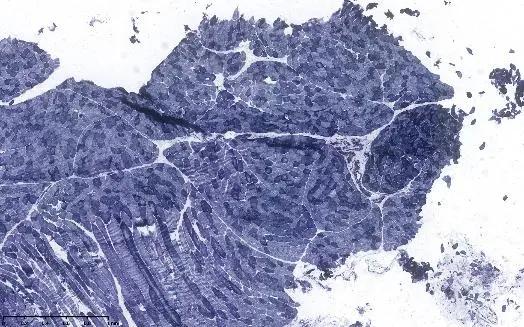

右侧股四头肌活检:骨骼肌呈慢性肌源性肌病改变,不能除外为肌营养不良。

王誉萱博士(病理科)点评:

低倍镜下可见肌束差异性较前次活检更大,肌肉组织被脂肪组织取代;高背景下可见核内移现象,可见大量萎缩肌纤维,以及核固缩聚集现象,膜蛋白免疫组化未见明显异常,提示慢性肌源性肌病改变。上述变化大多数出现在肌营养不良,但具体分型需结合临床及基因检测结果进一步判断。